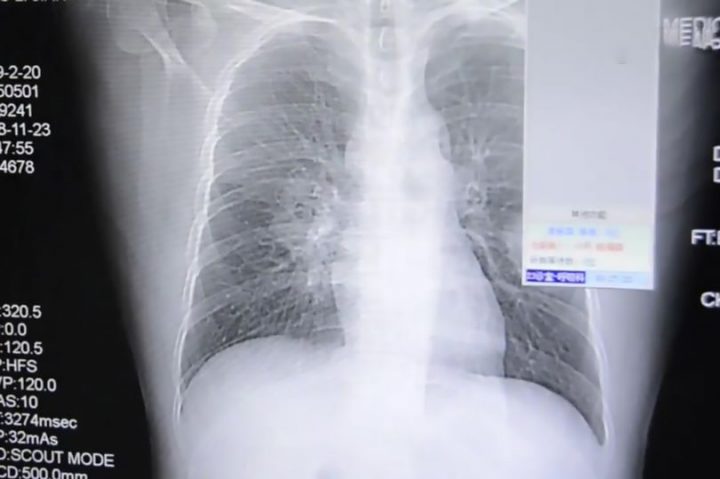

그러던 어느날 그는 극심한 가슴 통증을 느끼기 시작하다 결국 응급실에 실려가 치료를 받앗고 가슴 엑스레이 사진으로 그의 폐가 진균에 감염된 것을 확인할 수 있었다.

의료진은 그가 발 땀으로 인해 양말에 진균이 생겼으며 매일 양말 냄새를 맡은 행위로 인해 균이 폐 속으로 침입했다고 전했다.